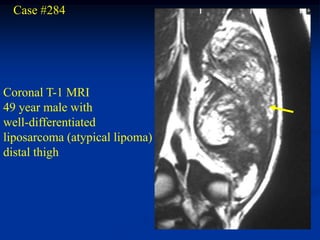

Case #284

Coronal T-1 MRI

49 year male with

well-differentiated

liposarcoma (atypical lipoma)

distal thigh

Sagittal T-1 MRI

Axial T-2 MRI

Case #284 Coronal T-1MRI 49 year male with well-differentiated liposarcoma (atypical lipoma) distal thigh